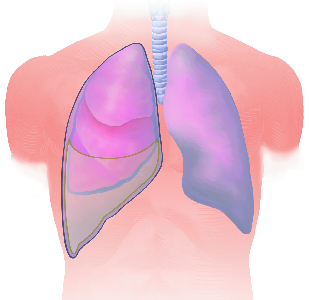

Detailreiche Fotografien aus der medizinischen Praxis ergänzen die Texte; moderne, genaue,

wissenschaftliche Zeichnungen geben Einblick in die Anatomie und die Funktion der Lunge und

anderer Organe.